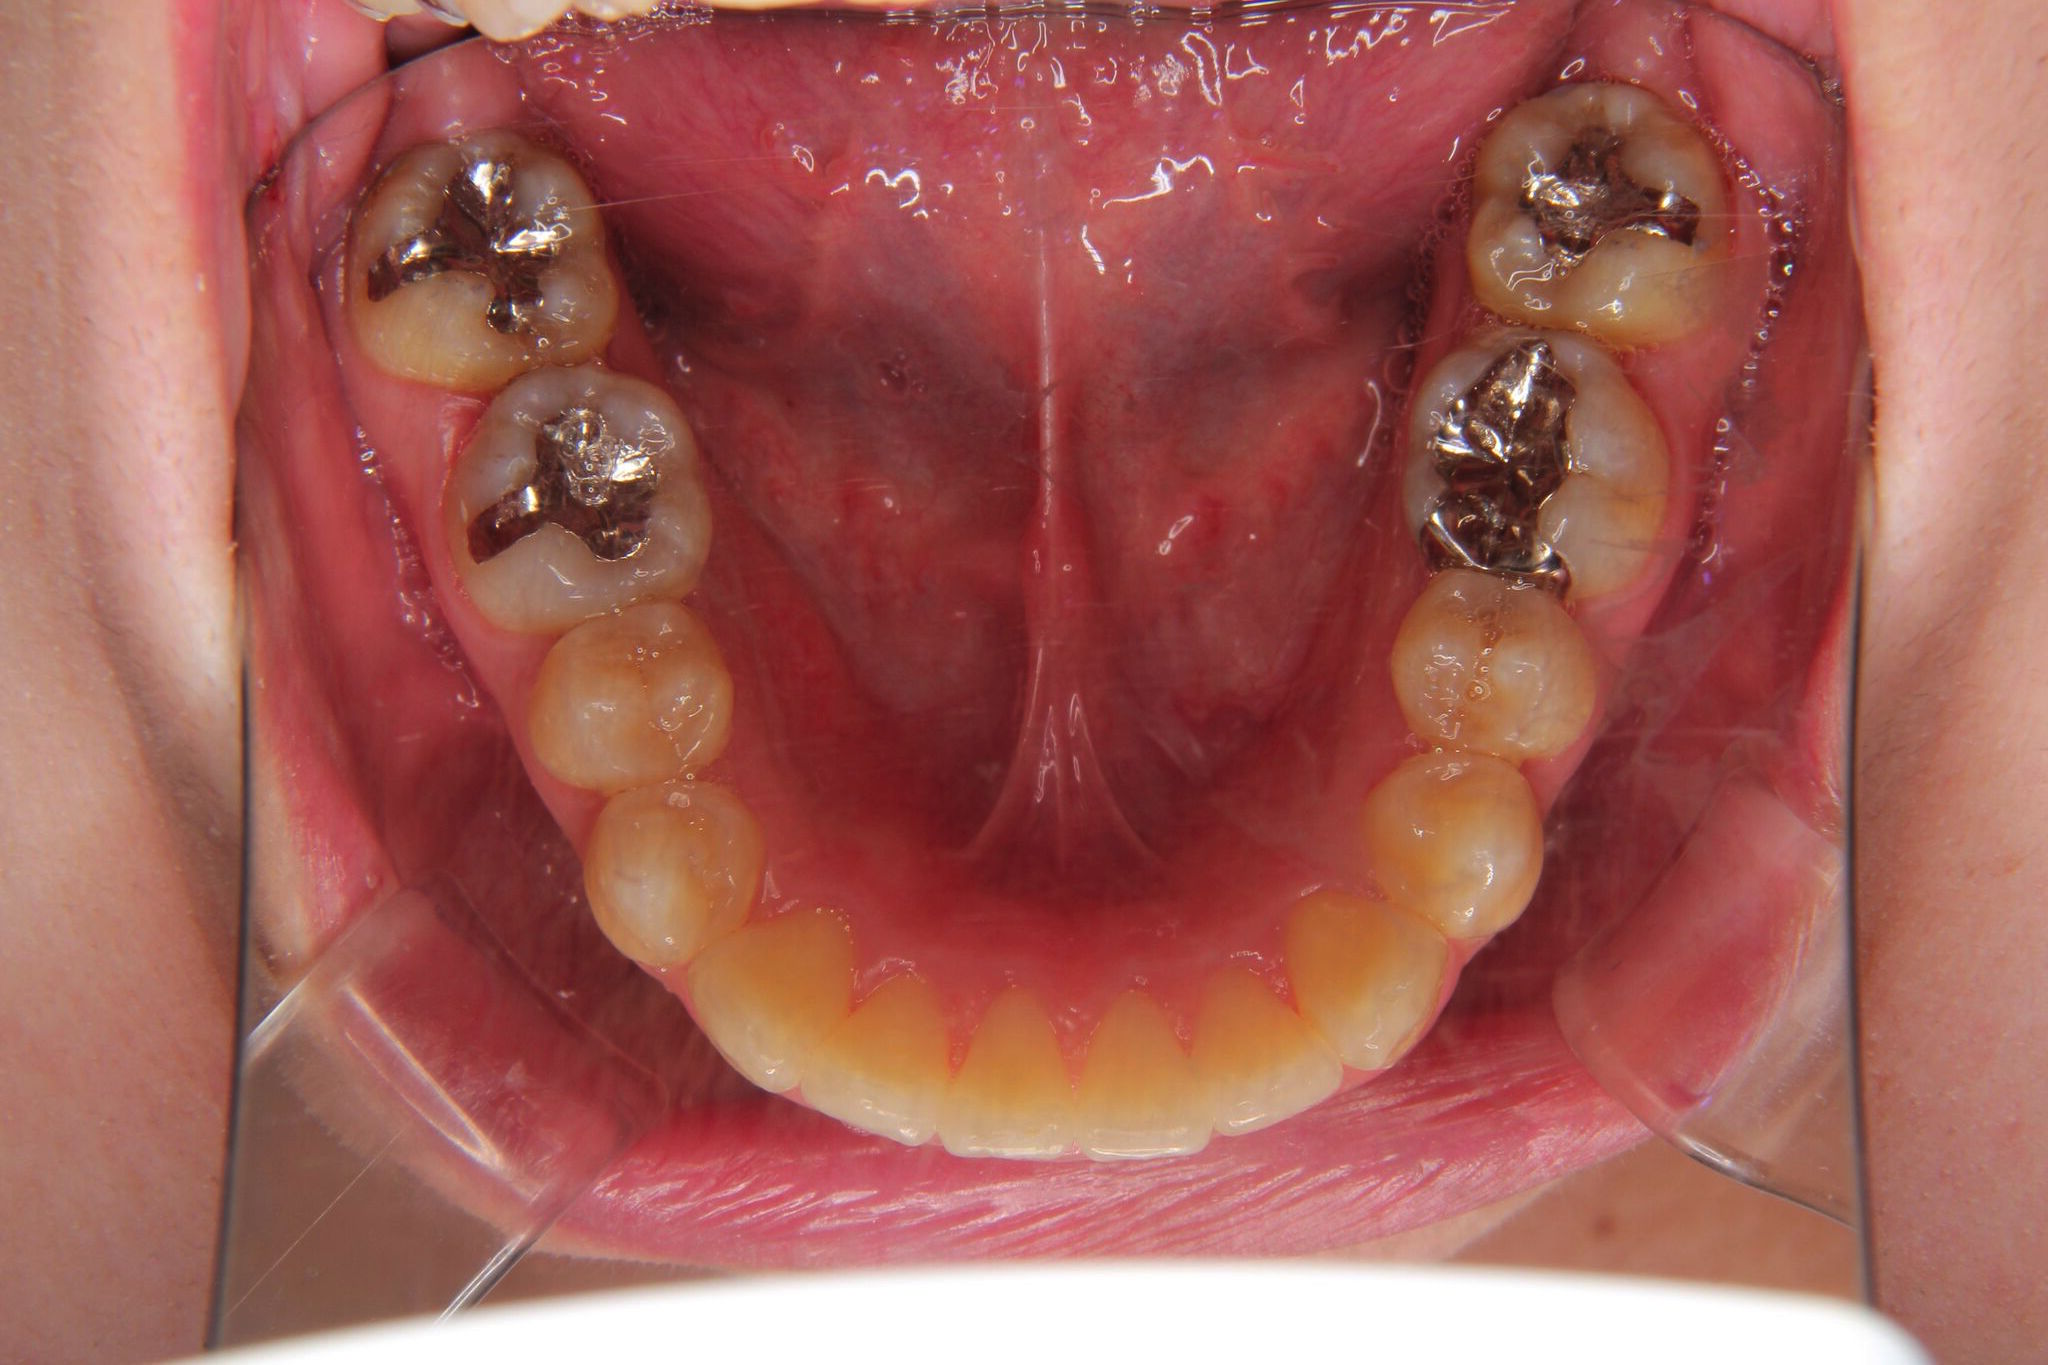

- 治療前 治療後

下の前歯に叢生(凸凹)がかなり認められました。

インビザラインによるマウスピース矯正にて、コントロールしました。

噛み合わせが深い(過蓋咬合)のため、下の前歯が内側に傾斜して、叢生ができている状態でした。このようなケースは、単純に歯の凸凹を改善しただけですと、すぐに装置をはずすと凸凹歯に後戻りしてしまうことが多くあります。

そのため、噛み合わせの高さを挙上しながら、凸凹を改善していく必要があります。

また、過蓋咬合は、下顎の自由運動領域が少なくなり、下顎が後方に後退する傾向にあります。下顎が前歯によって後ろに押し込められて、顎の関節が後ろの骨に圧迫され、痛みがでたり、音がカクカクなるなどの症状が出ることがあります。

歯並びは、歯だけの問題ではなく、顎の位置関係も重要です。